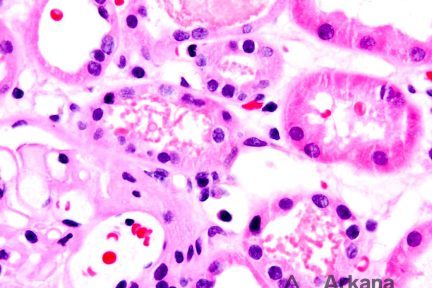

What is your diagnosis for this patient with nephrotic syndrome? …

Diagnose This (August 3, 2020)